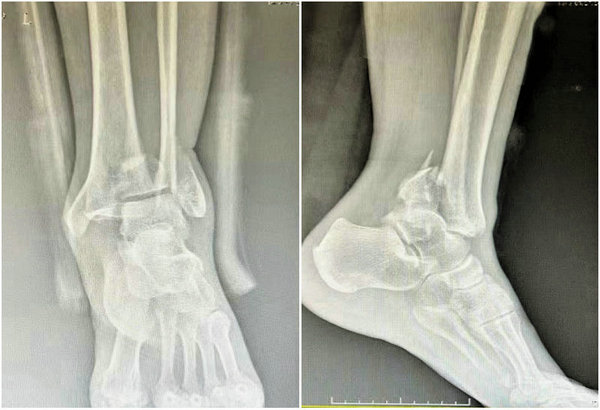

术前X线影像